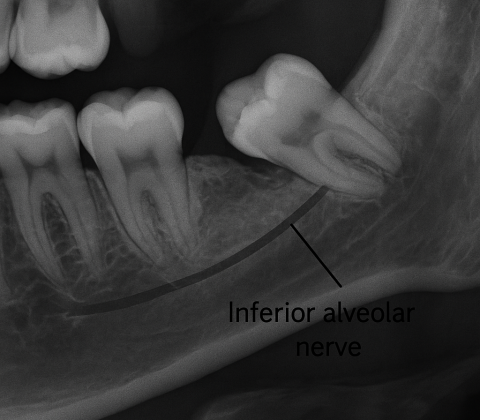

دندان عقل روی عصب؛ جراحی، هزینه، ریسک و نحوه تشخیص تخصصی

دندان عقل که معمولاً بین ۱۷ تا ۲۵ سالگی میروید، در بسیاری از افراد بهصورت نهفته، نیمهنهفته یا رویش کج دیده میشود. یکی از نگرانیهای